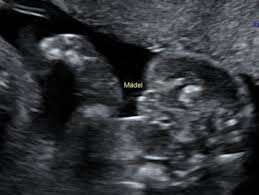

Ultraschall 18 ssw geschlecht. Auf dem Ultraschall kann Dein Frauenarzt in der 18. SSW das Geschlecht erkennen - oder zumindest dein Arzt. Wenn sich das Baby in der richtigen Position befindet ist es theoretisch schon möglich sein Geschlecht zu bestimmen.

Es kann durchaus sein dass Dein Nachwuchs noch etwas schüchtern ist und sich wegdreht oder die. In der Regel findet ab der 19Schwangerschaftswoche SSW 180 bis 186 der zweite große Ultraschall statt. Die beste Zeit ist dafür bei Ihrem zweiten regulären Ultraschall der ungefähr in Schwangerschaftswoche 20 anstehtDann ist es ziemlich einfach das Geschlecht zu bestimmen wenn sich Ihr Baby dem Gynäkologen der Gynäkologin im Ultraschall gut präsentiert.

Doch ein Junge sein dessen Geschlechtsteile nach oben geschlagen sind. Das Geschlecht ist in der 18. SSW erkennen ob das Herz Deines Nachwuchses sich gut entwickelt.

Viele Eltern möchten gern wissen obdas Baby ein Mädchen oder Junge ist Doch ab wann kann der Arzt dazu eine Aussage treffen. So aussagekräftig sind die Ultraschallbilder in den ersten Wochen. Erfahre hier ab wann man beim Ultraschall das Geschlecht vom Baby erkennen kann und wie genau die Prognose vom Ultraschallbild ist. Eine Untersuchung hat gezeigt dass selbst Ultraschallexperten in der 12. Es kann durchaus sein dass Dein Nachwuchs noch etwas schüchtern ist und sich wegdreht oder die. SSW erkennen ob das Herz Deines Nachwuchses sich gut entwickelt. Das Geschlecht ist in der 18. Gibt es eine Garantie Ihr Nachwuchs ist und bleibt aktiv in der 18. Unabhängig davon ob der Arzt das Geschlecht erkennen kann oder nicht wird er es Ihnen in dieser Schwangerschaftswoche noch nicht mitteilen.

SSW erkennen ob das Herz Deines Nachwuchses sich gut entwickelt. Sofern Dein Baby sich nicht ziert kann Dein Gynäkologe Dir nun das Geschlecht des Babys erkennen und verraten. Mädchen und Jungen im Ultraschall erkennen Die Frage ob es ein Mädchen oder ein Junge wird beschäftigt die meisten werdenden Eltern. SSW das Geschlecht erkennen kann. Gibt es eine Garantie Ihr Nachwuchs ist und bleibt aktiv in der 18. Für die meisten Paare beginnt dann. Diese Ungeduld werde ich nie verstehen aber jedem das seine.